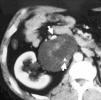

Diagnóstico de feocromocitoma mediante tomografía computarizada

Diagnosis of pheochromocytoma by computed tomography

E. Vázquez Muñoz, M. Atienza Saura, F.J. Barbado Hernández, M. López Rodríguez

Servicios de Radiodiagnóstico y de Medicina Interna. Hospital Universitario La Paz. Madrid. España